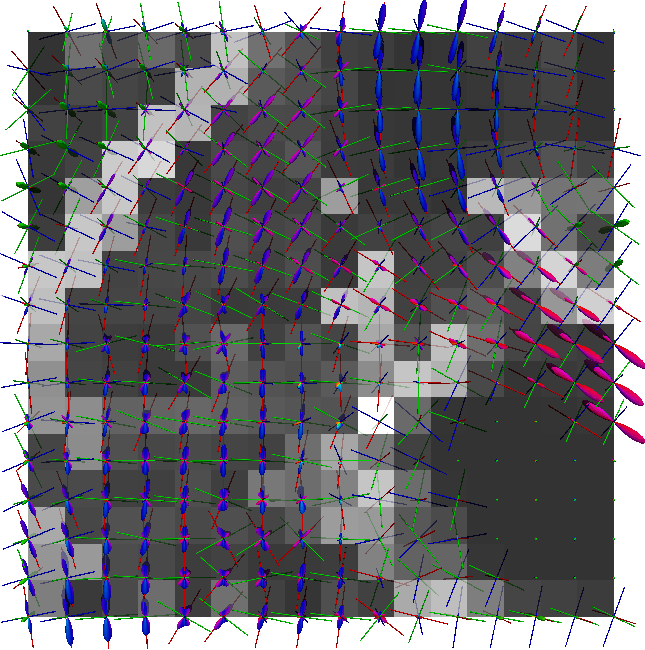

Non-negative spherical deconvolution (NNSD) (Cheng et al., 2014) is performed to estimate non-negative fiber ODFs from three-shell DWI data. NNSD works for multi-shell data. It is more robust to noise, and the obtained fiber ODFs (fODFs) in isotropic regions are closer to the isotropic spherical PDF, compared with conventional constrained spherical deconvolution (Tournier et al., 2007). After obtaining the fODFs by NNSD, the peaks are detected from the estimated fODFs with GFA larger than , as described in Section 3.4. OO and OD are calculated from the spherical harmonic representation of fODFs along their principal peaks as shown in Algorithm 1. The second row in Fig. 11 demonstrates FA from tensors estimated by DTI, OO and OD from fODFs estimated by NNSD, and the total distortion map estimated from the local orthogonal frames of fODFs. Fig. 12 and 13 show the close-up views of fODFs, local orthogonal frames, and the six proposed indices for the red and blue regions in Fig. 11, where the region shown in 12 is also visualized in the DFA pipeline in Fig. 1. The fODF glyphs are colored by using its sampled directions. The three orientations in the local orthogonal frame in each voxel are visualized by using three tubes in red, green, and blue colors respectively. There is no local orthogonal frame in some voxels because those voxels have GFA values lower than . These figures show the following: 1) OO is high in anisotropic areas with well-aligned directions, while OD is high in isotropic or crossing areas. 2) The four orientational distortion indices are low in areas with well aligned principal directions, and zero in isotropic voxels without peaks. Distortion indices are high in voxels where the principal directions in its local neighborhood change largely. 3) The central voxels in red region is the crossing area of the Corpus Callosum from left to right and Fornix that goes through the coronal slice. The twist index showed high value in this crossing area as expected.

We perform whole brain streamline tractography on the estimated fODF field using mrtrix (Tournier et al., 2012) 888http://www.mrtrix.org/. The voxels with GFA larger than are used as seed voxels to generate tracts by using tckgen in mrtrix. All other parameters are default parameters in mrtrix. The obtained fiber tracts are then visualized by using trackvis 999http://trackvis.org. Fig. 14 and 15 demonstrate the tracts respectively cross two given ball ROIs. The tracts are colored by using the proposed six scalar indices. Note that the proposed scalar indices are calculated based on estimated fODFs, not based on fiber tracts. It can be seen that 1) OO is high in areas with well aligned fibers, while OD is high in crossing areas and distortion areas; 2) distortion indices are low when fibers are well aligned; 3) the total distortion index is high in areas with highly curved fibers or crossing fibers. 4) although splay, bend, twist indices may be separable (e.g., one is large while another one is close to zero) in synthetic data, in real data, these three types of distortions normally occur together, especially for bending and splaying. 5) the ROI in Fig. 14 is the crossing area of the Corpus Callosum and the Fornix, where all distortion indices have high values, especially for twist and total distortion indices. This finding agrees with Fig. 12.